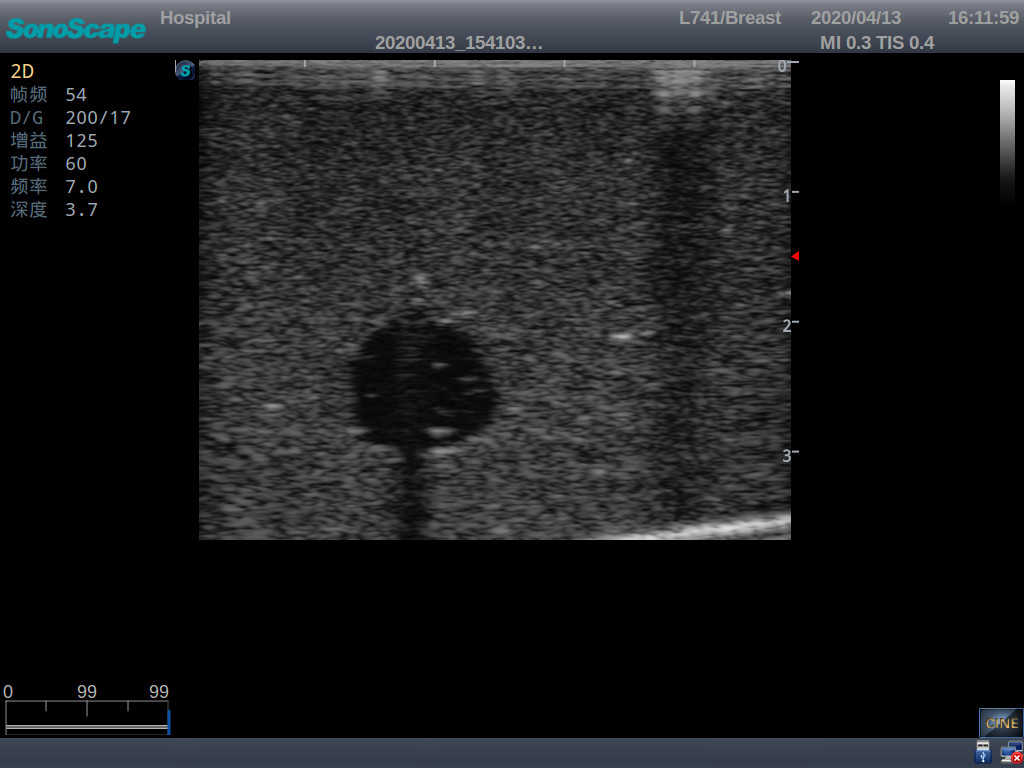

Outline

The Wearable Breast Ultrasound Examination Model allows users to develop and practice the skills necessary to gain proficiency in breast palpation, using ultrasound for normal and abnormal imaging and biopsy. It simulates adult female breasts with realistic size and appearance.

2)  Each model contains 8 space-occupying lesions of varying sizes, different in touch, elasticity and ultrasonogram

4) Biomimetic material allowing users to see clear and real normal tissues and space-occupying lesions that are hyperechoic, hypoechoic and isoechoic as they would see in the clinical environment